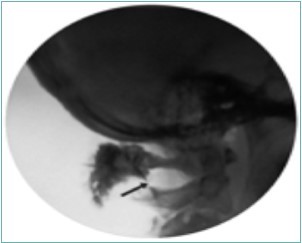

Because of the proximity to the vertebral artery and the potential risk of intravascular injection, few interventionalists have been interested in AA injections, and, since the proximal GON travels over the posterior arch of the atlas, even fewer have been interested in direct injections of the proximal GON. In an effort to avoid the “locked-in” syndrome complication seen with occipital injections, Dr. Gabor Racz developed a suboccipital approach to the suboccipital space in 1982, which has recently become more popular7, 8. A curved, bullet-tipped needle with side port injection, attached tubing, and wings (dubbed the “Stealth needle”™ because of its resemblance to the Stealth bomber) Figure 5 is used to approach the suboccipital triangle from above. Since the underlying pathology is usually bilateral, the procedure is usually performed bilaterally.The patient is positioned prone on the fluoroscopy table, with the neck in flexion; the hair is pulled cephalad, and the suboccipital area is sterilely prepped and draped. The inion and conjoined tendon are identified by palpation and the nuchal line is identified by fluoroscopy; the entry site should be 2cm lateral to the midline on the nuchal ridge. After making sure by palpation that the planned entry is not directly over the occipital artery, a small skin wheal of local anesthetic is injected via a 30g needle. Because the galea is so strong, an 18g needle is used to create a small stab incision in the scalp and deep fascia to facilitate the entry of the blunt-tipped needle. Standing at the head of the bed, the Stealth needle is held by the wings like a butterfly IV needle, and, with tip facing down and toward the feet Figure 6 the needle is advanced caudally. The needle position is initially identified on an anterior-posterior fluoroscopy view, with the target medial to the superior pars of C2 Figure 7 The needle is advanced through the muscle and fascial layers of the trapezius and semispinatus with confirmation of location on lateral view, aiming for the superior lamina of C2 at the level of the spinous processes Figure 8. Contrast is injected to verify needle placement Figure 9 followed by 10 cc of local anesthetics and steroids (4.5ccs 0.2% ropivicaine, 4.5ccs 1% lidocaine, and 10mg of dexamethasone on each side) to perform an adhesiolysis, freeing up the greater occipital nerves Figure 10 Because this technique is usually performed bilaterally, lower concentrations of local anesthetic are used to avoid toxicity issues.

Figure 10.Lateral fluoroscopic image showing the final contrast spread; the arrow shows the outline of the greater occipital nerve at the level of the inferior oblique capitus muscle. Image Courtesy of Gabor Racz, MD